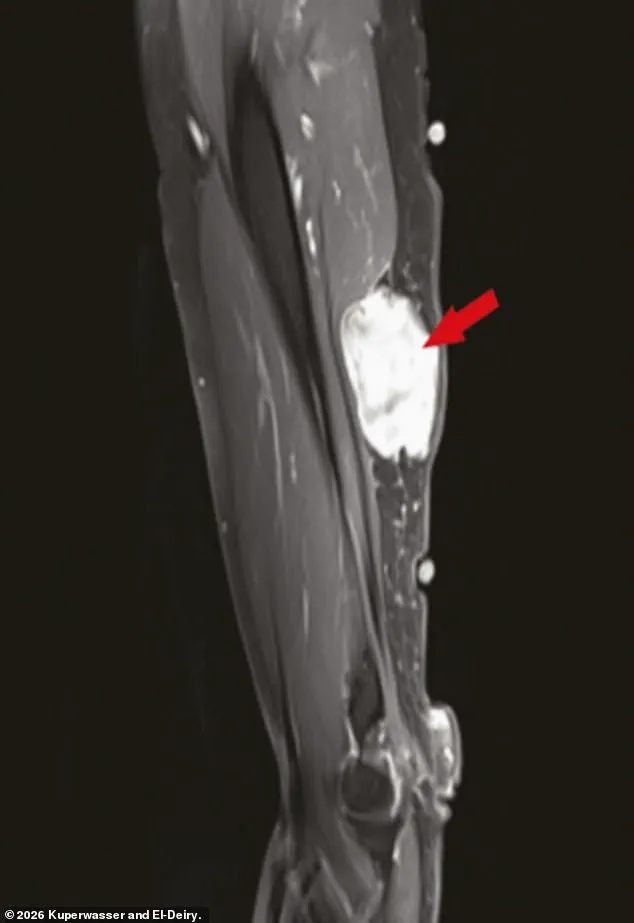

These included instances of slow-growing cancers reactivating after vaccination and localized reactions near injection sites, such as tumors developing in the arm.